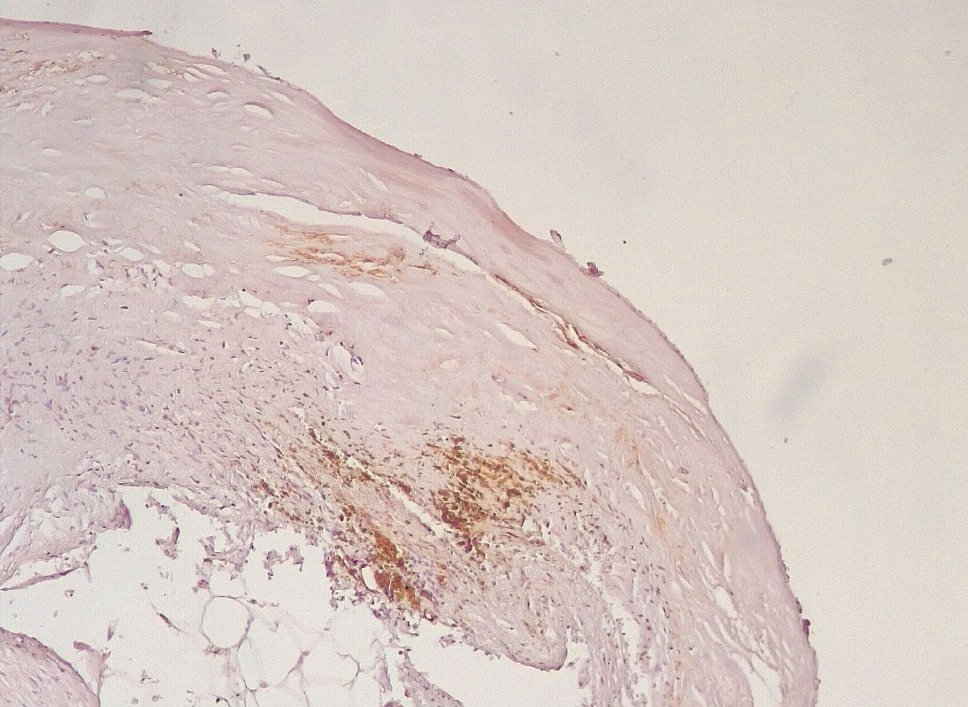

Обращало внимание, что в местах «оголенного» эндотелия КА отмечалась слабая экспрессия белка CD31, что указывало на выраженные дистрофические и некробиотические изменения клеток (рис. 2). При этом экспрессия ФВ была яркой, выраженной на всем протяжении интимы КА (рис. 3).

Сохранялась резковыраженная яркая экспрессия ФВ как со стороны интимы, так и субинтимально, в участках альтерации атером (рис. 8). В то же время экспрессия белка CD31 была негативной на всем протяжении стенок КА.